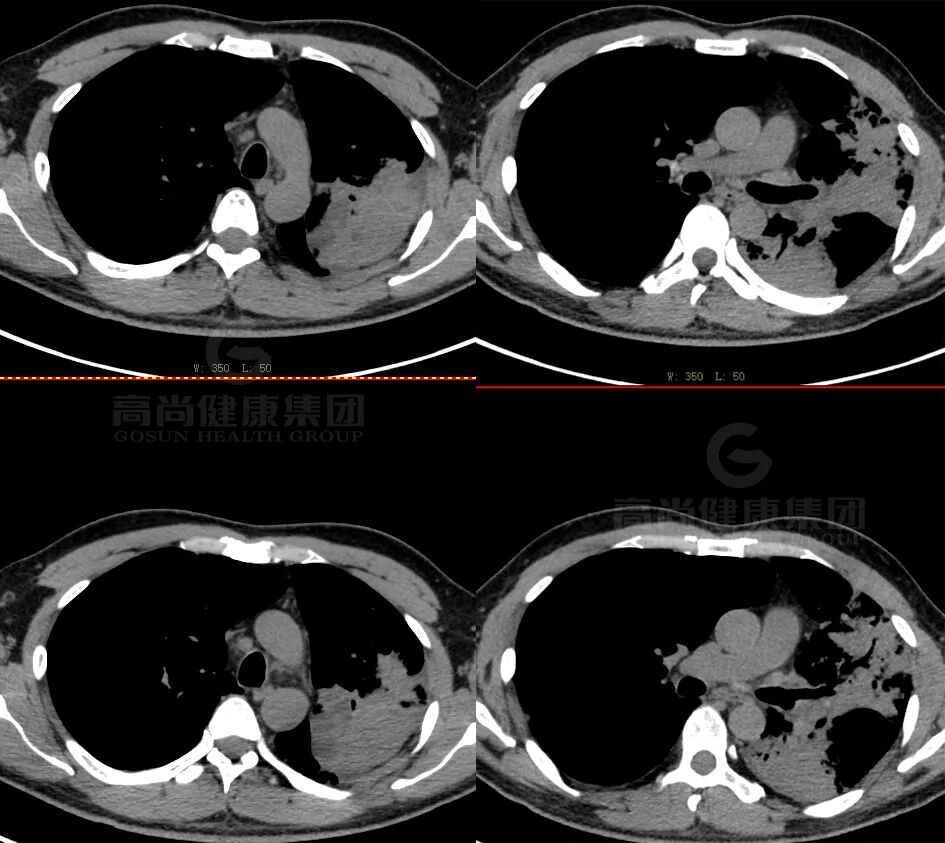

PET/CT 图像

纤支镜病理

肺腺癌(高分化)。